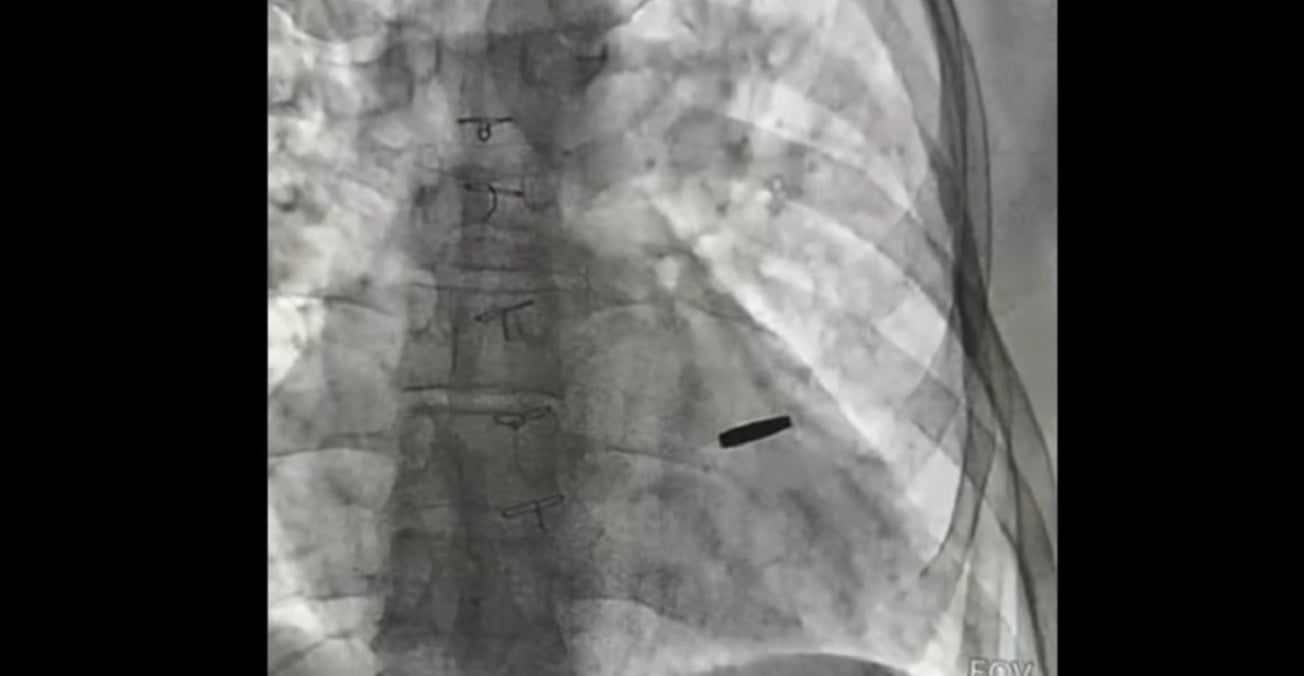

На рентгенівському знімку видно кулю у серці військового

Поранений боєць з кулею у серці потрапив у полон, де провів три роки. Кулю київські кардіохірурги видалили. На третій день після операції він вже гуляв на подвір’ї Інституту серця. На щастя, вона не завдала бійцю серйозних ушкоджень, тож лікарі сподіваються, що захисник проживе довге і щасливе життя.